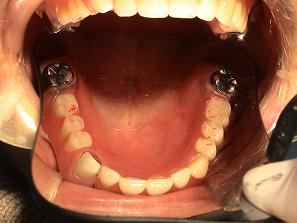

2. 作製したバネなし入れ歯

(バルプラスト)です